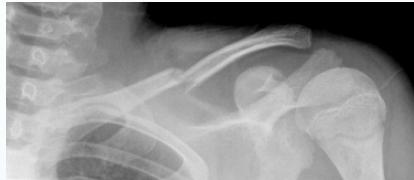

- Birth injury

- Fall on outstretched hand

- Heals well conservatively

- Sling or figure-of-8 bandage (better)